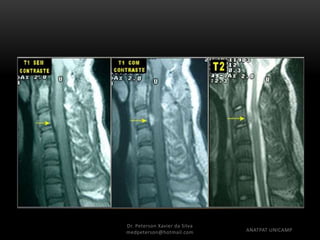

Diagnóstico por Imagem

• RNM

– Heterogêneo em T1, Hiperintenso ou hipointenso em T2,

realce heterogêneo ao contraste, restringe a difusão,

pico de colina a espectroscopia

Diagnóstico por Imagem •Tomografia – Imagem bem definida, linha média em fossa posterior, espontaneamente hiperdenso, realce homogêneo ao contraste • RNM – Heterogêneo em T1, Hiperintenso ou hipointenso em T2, realce heterogêneo ao contraste, restringe a difusão, pico de colina a espectroscopia Dr. Peterson Xavier da Silva Dr. Peterson Xavier da Silva medpeterson@hotmail.com